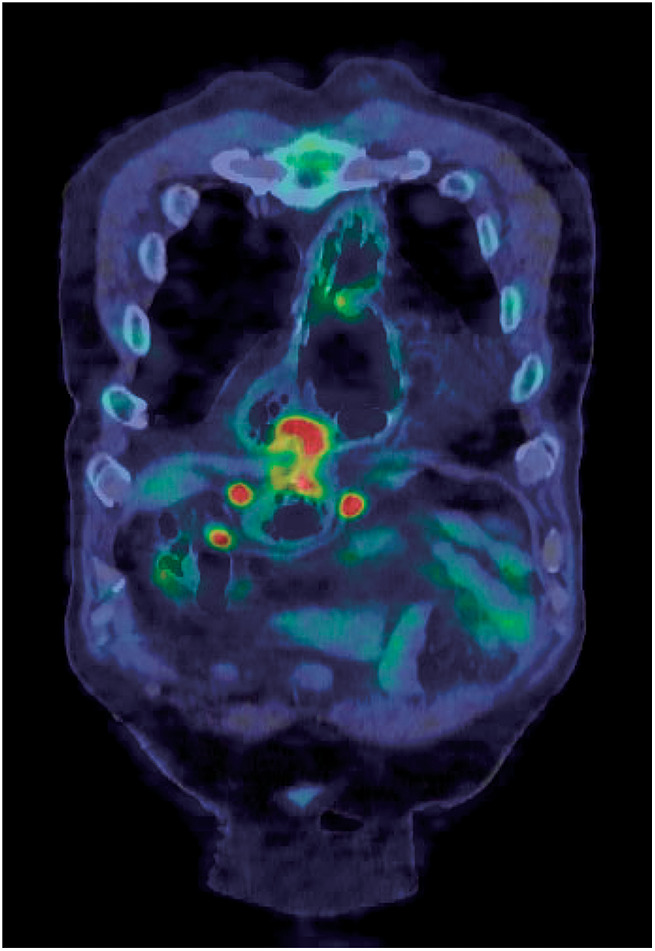

The incidence of gastric tube cancers has increased due to improved survival rates in patients after esophagectomy. However, the optimal surgical approach for gastric tube cancer remains controversial. Here, we report the case of a 70-year-old man with advanced gastric cancer arising from a retrosternally placed gastric conduit, 12 years after thoracic esophagectomy for esophageal cancer. Total resection of the gastric conduit was performed with robotic assistance. Although the working space was limited, secure resection was possible. Continuous en bloc mobilization was achieved with neck dissection, and reconstruction was performed via the same retrosternal route using the ileocolon. The patient was discharged on the 14th postoperative day without any adverse events. Robot-assisted surgery can overcome the technical limitations of laparoscopic mediastinal surgery and has advantages such as improved ergonomics, comfort, and elimination of hand tremors, and therefore may be an option for future minimally invasive surgeries.